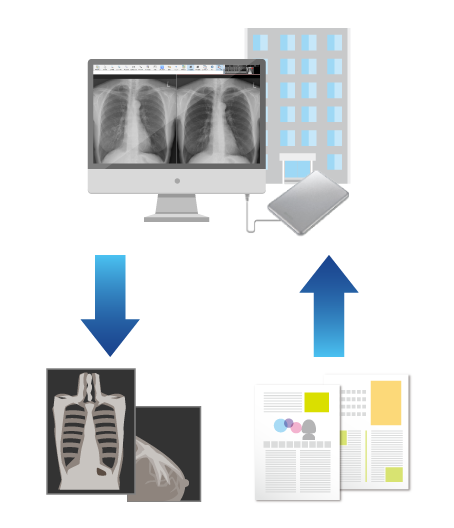

外部読影も簡単にシステム化したい!

- セキュリティ機能付きのメディアを使い、外部でもレポート入力可能

- ネットワークも事前のソフトウェアインストールも不要!手軽に読影開始

- メディアからビューア&レポートが起動し、自宅や勤務先のPCで所見入力

- ネットワーク環境下では、オンラインでのデータ授受も可能

オフラインレポート

データ+システム

(セキュリティ機能付き)

急な医師の交代や、環境の変化にも簡単に対応可能。

外部に多く読影依頼している施設は必見です!